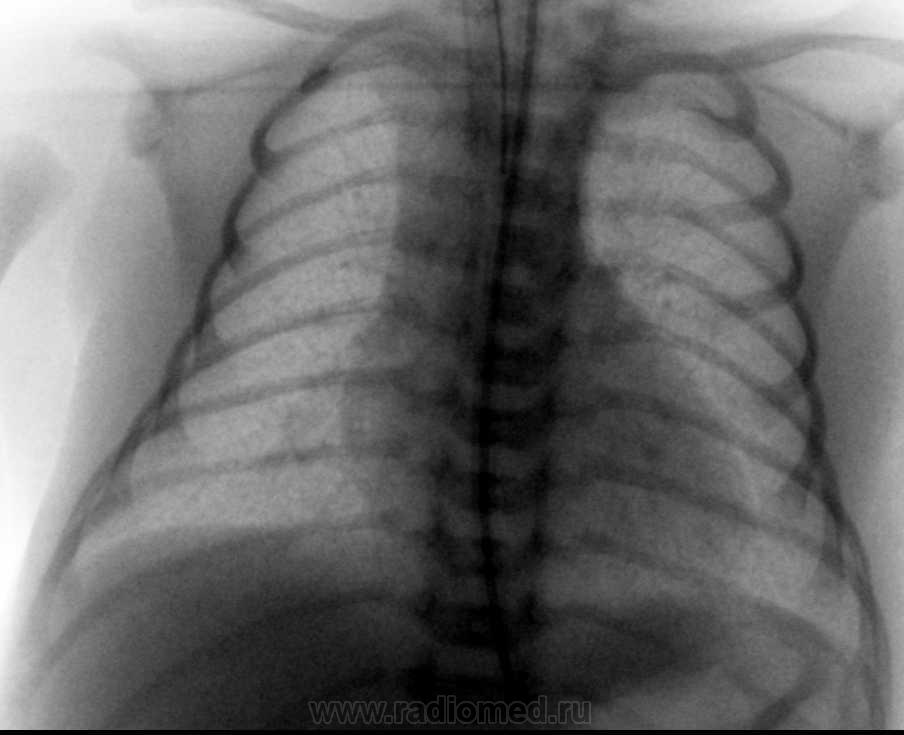

Новорожденный в сроке 30 недель, в данный момент находиться в детской реанимации, к нам сегодня обратился педиатр с просьбой повторно проанализировать обзорную рентген-картину органов грудной клетки. В анамнезе у мамы носительства цитамегаловируса и токсоплазмоза.  На данный момент у меня мысли о наличие генерализованной формы токсоплазмоза у ребенка в легких ввиде сепсиса, возможно я ошибась, возможно у кого имеются другие мысли по данному случаю?

Снимок от 2.03.10г.

Мелкоочаговая мономорфная диссеминация.